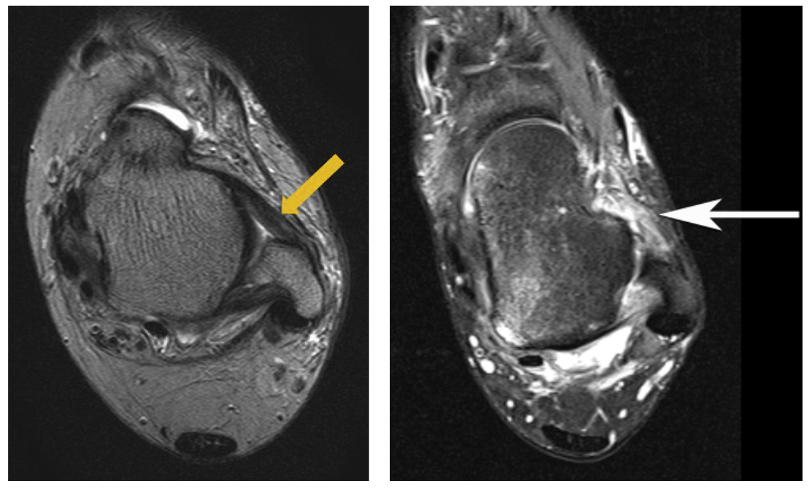

Le bilan d’imagerie permet de confirmer la laxité retrouvée à l’examen clinique.

Il permet aussi d’établir une cartographie précise des lésions ligamentaires et des lésions associées (tendinopathies, conflits osseux, lésions du cartilage).

Plusieurs examens peuvent être proposés : un arthroscanner, une I.R.M, une échographie ou des radiographies dynamiques.